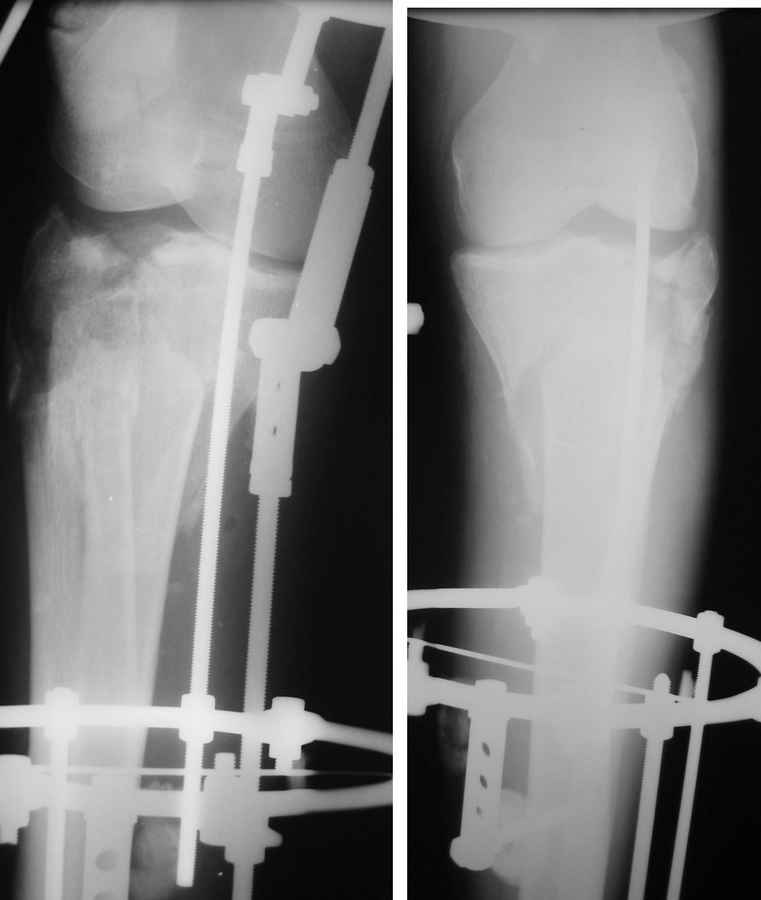

Саша, а в чем конкретно неясность? Надо полагать, вопрос не про общие принципы лечения переломов типа Schatzker VI или C3 по классификации AO, которые можно найти в любом руководстве?

Состояние мягких тканей оказалось принципиальным в разработке плана операции.

Очаг некроза 4 на 5 см по передней поверхности голени не оставил никакого варианта кроме внешнего остеосинтеза.

Но решили делать в 2 этапа. Первый - восстановить ось и дать костной крошке в проксимальном отделе консолидироваться.

Второй - собственно артродез.

Но по результатам первого этапа думаем дать пациенту попользоваться ногой. А там посмотрим.

Почему??? Есть сухой некроз по передней поверхности, но вне зоны возможных хирургических доступов...-

Для первого этапа достаточно. Через 5-10 дней мы бы приступили к следующему этапу. А именно, фиксация из ограниченного заднемедиального доступа 1\3 трубчатой или рекон пластиной медиального фрагмента, и остеосинтез наружного мыщелка из второго тоже ограниченного латерального доступа без артротомии, под контролем ЭОПа..... Сухой некроз в данном случае не являлся бы серьезной помехой для внутренней фиксации (во всяком случае, судя по имеющимся фото)

Я думаю, это не повод сразу думать об артродезе... Конечно уже прошло много времени. Но до месяца у нас есть опыт вполне удачных реконструкций и "переделок"...

P.S. безусловно, с двумя пластинами LCP, каннюлироваными винтами, хроносом все это дорого... Но того же анатомического и функционального результата можно достичь, используя вместо пластин аппарат Илизарова, и разрезы для репозиции тогда нудны совсем маленькие .

Очевидно, что в реале картина была бы гораздо хуже, чем на рентгене. Каким бы способом мы не вскрыли зону повреждения, обнаружили бы дефект, который нужно чем-то замещать и далее по нарастающей. Пластина наверняка вылезла бы в зону некроза и т.д и т.п. Срок тоже уже к месяцу подползал...